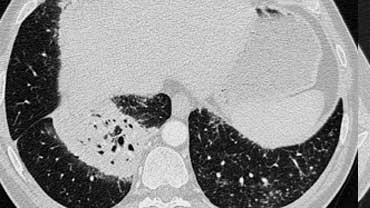

Bệnh nhân ở giai đoạn I.

Có hạch to rốn phổi và cạnh khí quản, không có dấu hiệu tổn thương nhu mô phổi.

Sarcoidosis: hình ảnh điển hình với các nốt dọc theo bó mạch phế quản và các khe liên thùy. Lưu ý hạch vôi hóa một phần ở rốn phổi trái.